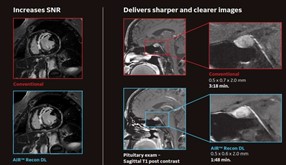

L’IRM qui améliore l’expérience thérapeutique, la qualité de l’image et l’efficacité

GE Santé ne concentre pas son attention uniquement sur la mise à disposition d’une grande technologie susceptible de donner de meilleurs résultats thérapeutiques. Il cherche à améliorer l’expérience thérapeutique et à rendre les équipes cliniques plus productives afin qu’elles prodiguent des soins de manière plus efficace et produisent des examens de qualité supérieure. Pour répondre à ces besoins, GE Santé a développé la famille AIRmc qui s’appuie sur les produits suivants: l’AIR Coils, qui bonifie l’expérience thérapeutique et accélère les examens, l’AIR Workflow, qui améliore la productivité de l’IRM avec des applications de flux de travail intelligentes telles que l’AIR Touchmc (positionnement automatique du patient propulsé par l’IA) et AIR xmc (prescription intelligente des tranches d’IRM actionnée par Deep Learning), et enfin l’AIR Recon DL, qui améliore la qualité d’image.

AIRmc Recon DL, une application Edison fournissant TrueFidelitymc, une première en technologie de reconstruction de l’image d’IRM basée sur l’apprentissage profond de GE Santé conçue pour simplifier ce choix en améliorant le rapport signal sur bruit et la netteté de l’image tout en abrégeant la durée des examens. Des examens moins longs réduisent les listes d’attente et aussi le temps passé par le patient sur la table. Dans bien des cas, cette technologie peut réduire de moitié ou du tiers le temps d’une IRM. Les cliniciens et les technologues n’auront plus à sacrifier la qualité de l’image à la durée de l’examen. Cette application a été développée au Canada et utilise un réseau neuronal formé sur la base de dizaines de milliers d’images de la plateforme d’IA Edison de GE Santé.

Il ne s’agit pas d’un filtre ou d’une technique de post-traitement. Cette application est intégrée directement dans le pipeline de reconstruction dans lequel le modèle du réseau neuronal est appliqué aux données pour supprimer le bruit et les artéfacts d’ondulation avant la formation de l’image finale.

« La différence observée quant à la qualité de nos examens et au temps épargné est énorme, a déclaré le Dr Naeem Khan, M.D., chef du Département de l’imagerie diagnostique du IWK Health Centre. Avec l'AIR Recon DL, nous obtenons des images de qualité supérieure en moitié moins de temps et si nous désirons obtenir encore plus de qualité pour bien voir les détails dans certaines circonstances, il suffit de prolonger la séquence d’une durée qui restera quand même inférieure à la durée d’une séquence conventionnelle sans l’AIR recon DL. Nous obtiendrons une qualité nettement meilleure. »

L’AIRmc Workflow améliore la productivité de l’IRM grâce à des applications intelligentes de flux de travail, telles que l’AIR Touchmc (positionnement automatique du patient propulsé par l’IA) et l’AIR xmc (prescription intelligente des tranches d’IRM actionnée par Deep Learning) pour tous les types d’examens du cerveau et du genou).

Les produits AIRmc se distinguent par leur complémentarité. Chaque produit profite du potentiel des autres, ce qui crée une chaîne d’innovation qui les relie entre eux et transforme l’expérience d’IRM. Cette nouvelle expérience qu’offre GE soutiendra les services d’imagerie d’IRM pour atteindre et même dépasser leurs résultats essentiels.